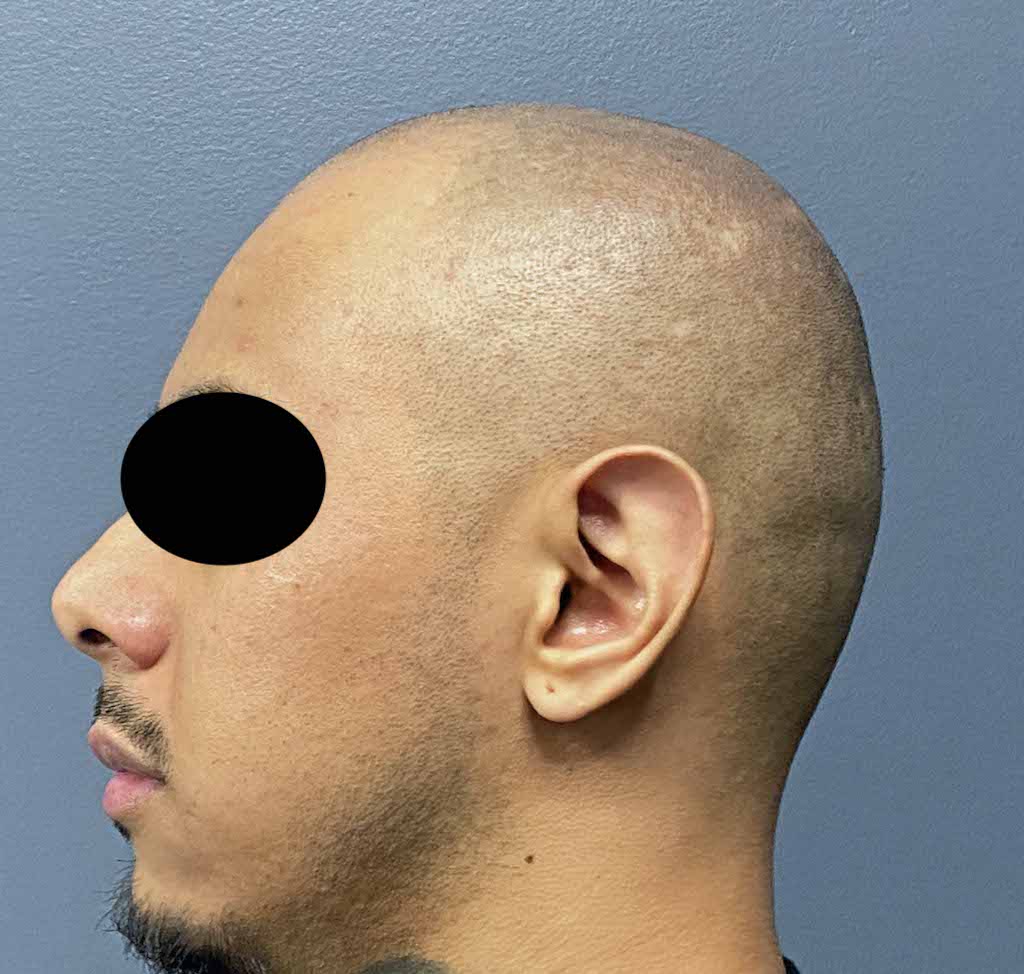

Patient 100

Desire for reshaping of an asymmetric flat back of the head in a shaved head male.

A combined back of the head reshaping procedure was done with a custom skull implant, sagittal ridge reduction and a right temporal muscle reduction.

Desire for reshaping of an asymmetric flat back of the head in a shaved head male.

A combined back of the head reshaping procedure was done with a custom skull implant, sagittal ridge reduction and a right temporal muscle reduction.